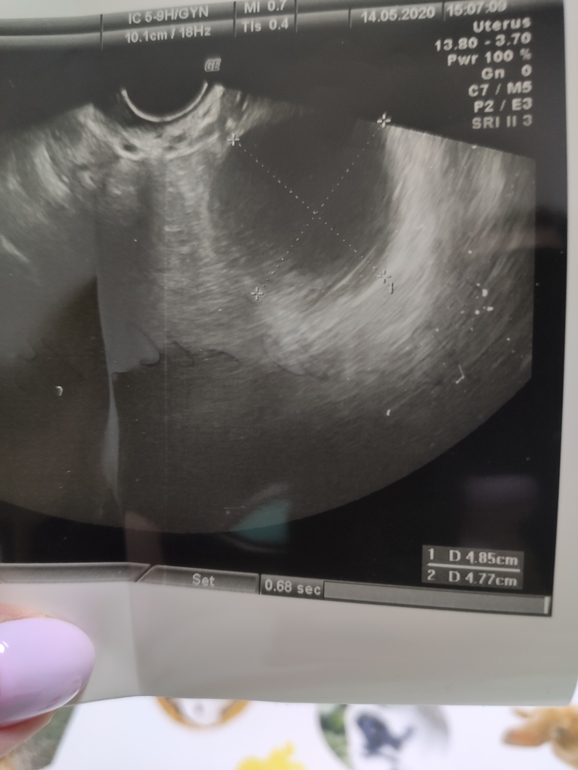

Овуляция( тесты на овуляцию)Девочки привет! Так старались в этом цикле с мужем и все шло так хорошо, тест улыбался, яб, все как обычно, и вот спустя три дня после овуляции, сильно болит слева, на узи в левом яичнике киста ((( скорее всего фолликулярная? Узист не смогла ответить какая именно...просто смущает что было западение бт, а потом в один день резкий скачок до 37 ...обычно постепенно, я уже понадеялась ....может ли это быть киста жёлтого тела? Анэхогенное, почти 5 см в диаметре.

Так в чем суть. Неизвестно какая это киста, мне не сказали не знает узист вот так какая именно. Конечно я больше думаю что фолликулярная. Но е мое с чего тогда и грудь заболела сразу после овуляции как всегда и такой скачок бт с 36.6 до 37 был, как будто состоялась все таки О. Ну да ладно.